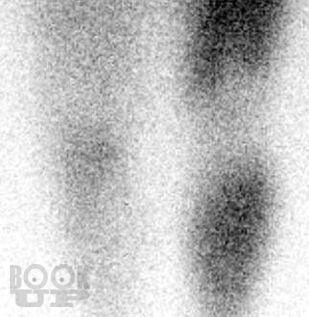

В настоящей монографии в сравнительном аспекте рассматриваются диагностические и дифференциально-диагностические возможности сцинтиграфии с неспецифическим туморотропным радиофармацевтическим препаратом и индикатором воспалительных процессов 199Tl-хлоридом. Авторами показана высокая эффективность сцинтиграфии с 199Tl-хлоридом в неспецифической индикации и дифференцильной диагностике опухолевых и воспалительных процессов опорно-двигательного аппарата, органов грудной клетки и прочих локализаций, приводятся диагностические и дифференциально-диагностические критерии этих процессов.